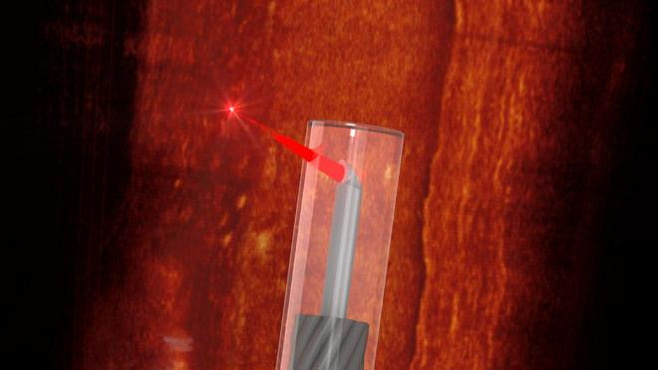

Международная команда исследователей разработала самый маленький в мире эндоскоп, способный проникать в сосуды для построения трёхмерной карты кровеносной системы – об этом

Представленное на этой неделе устройство получило диаметр меньше 0.5 миллиметра, причём в этот размер вошла и особая защитная оболочка. В состав эндоскопа также вошла напечатанная на 3D-принтере линза с боковым диаметром менее 0.13 миллиметров.

В качестве цели использования аппарата учёные назвали сканирование кровеносных сосудов на предмет жировых отложений и представление маршрута эндоскопа в виде 3D-карты.

Фото: University of Adelaide